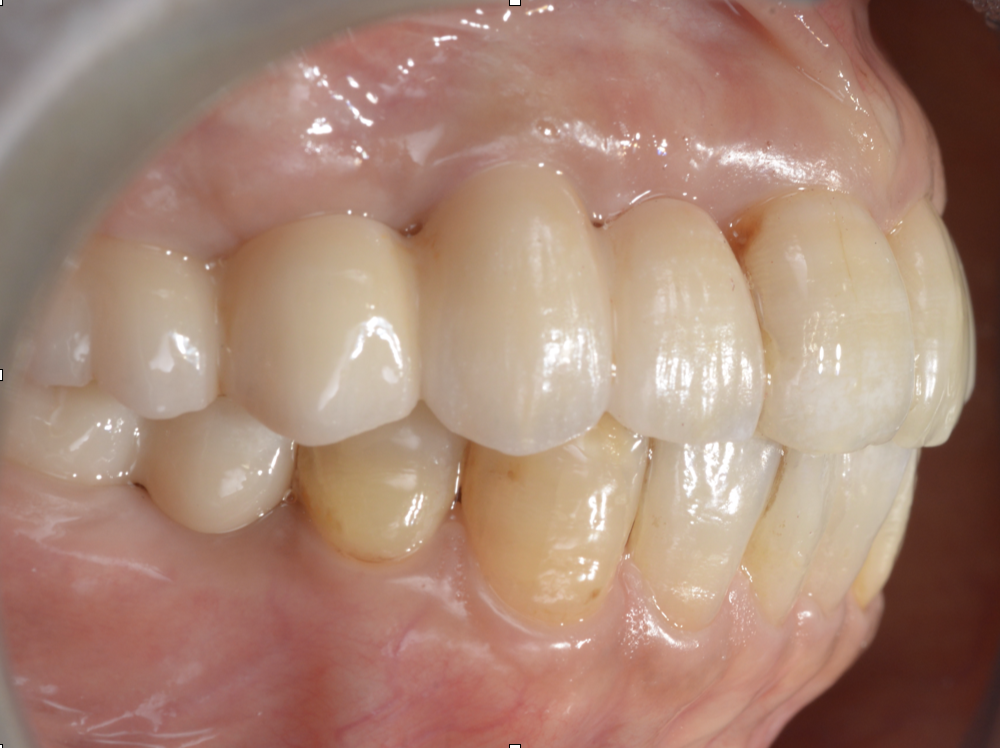

治療後

| 治療内容 | 初診時の考え方:原因は「歯」だけではなく“設計”のことがある 腫れや動揺があると、「歯周病だから」「根が悪いから」と言われがちですが、再治療で大切なのは なぜその状態まで進んだのかを整理することです。 補綴(被せ物・ブリッジ等)の設計や噛み合わせに無理があると、特定部位に力が集中して • 炎症(腫れ・排膿) • 動揺(グラつき) • 噛めない という状態に進行することがあります。 このケースも、力のかかり方を見直し、噛み合わせと補綴設計を再構成することが治療の軸になりました。 ⸻ 奥歯が噛めない → 前歯が働きすぎて切端咬合になっていた 患者様は「奥歯で噛めない」状態を補うように、前方で噛む癖がつき、 切端咬合(前歯同士がぶつかる噛み方)になっていました。 切端咬合は、 • 前歯が欠けやすい/すり減りやすい • 補綴が壊れやすい • 力の逃げ場がなくなる など、治療後の安定を難しくする要因になります。 そのため今回は、インプラント治療だけで完結させるのではなく、前歯の噛み合わせも作り直す必要がありました。 ⸻ 治療方針:本数を増やすのではなく“成立させる条件”を整える 患者様の条件(費用・怖さ・体の負担)を踏まえ、当院では • インプラントは3本に絞る • 上下ともにインプラントブリッジで噛める機能を回復 • 部分矯正で切端咬合を改善し、少ない本数でも成立する咬合へ • 可能な範囲で抜歯即時を選択し、外科を1回にまとめる という方針を採用しました。 ⸻ 治療のポイント①:部分矯正は“見た目”ではなく、設計を成立させるために使う 本数を絞った設計を成立させるには、力のかけ方(咬合設計)を整えることが重要です。 そこで、部分矯正で • 前歯の被蓋(かみ合わせ)を再構築 • 前歯に負担が集中しない状態へ • ブリッジに無理が出ない噛み合わせへ と調整し、少ない本数でも長期安定を狙える条件に近づけました。 ⸻ 治療のポイント②:上下インプラントブリッジ+材料選択(高強度ジルコニア) 上下ともにブリッジ設計の場合、材料と厚みの設計が安定性に直結します。 今回は、審美性や立体感はやや制限される可能性がある一方で、 強度を優先できる高強度ジルコニアを選択し、必要な厚みを確保しました。 「見た目の理想」よりも、まずは 噛めること/壊れにくいこと/長く使えること を優先した設計です。 ⸻ 治療のポイント③:抜歯即時で外科は1回にまとめる 患者様の「手術が怖い」「回数を減らしたい」という希望に対して、 感染や骨の条件を見極めたうえで、可能な範囲で抜歯と同日にインプラント埋入(抜歯即時)を行い、外科介入を1回にまとめました。 ※抜歯即時は、すべてのケースに適応できる方法ではありません。 ⸻ 治療後の経過(結果) • 噛めない状態が改善し、食事の不安が軽減 • 切端咬合を改善し、前歯の負担を減らす方向へ • 少ない本数でも成立するよう、噛み合わせと設計を最優先で再構成 ⸻ 担当医コメント 「理想形」だけを追うと、治療は大きくなりがちです。 今回のように、患者様の希望(負担・回数・費用)を尊重しながら、噛み合わせと設計を整えることで“成立させる治療”を選ぶことも大切だと考えています。 |